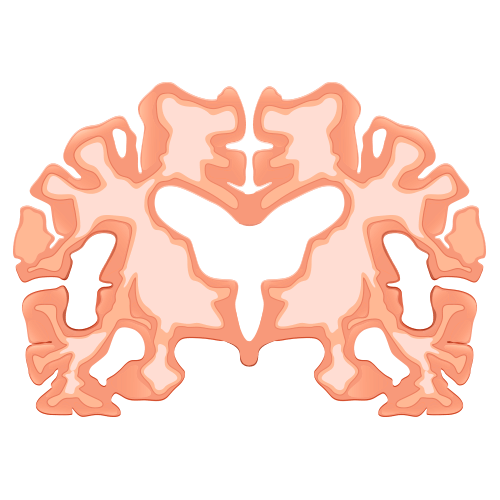

Impacto do Alzheimer no cérebro saudável